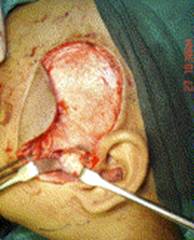

TMJ ANKYLOSIS SURGICAL MANAGEMENT, GAP ARTHROPLASTY WITH TMF FLAP